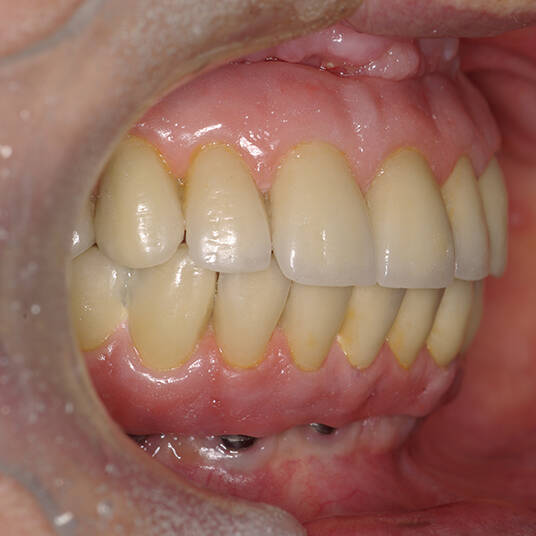

Na Clínica Pontes Odontologia, somos referência em implantes dentários em Fortaleza, oferecendo tratamentos de alta qualidade e tecnologia de ponta. Os implantes dentários são estruturas de titânio posicionadas cirurgicamente no osso maxilar ou mandibular para substituir as raízes dos dentes ausentes. Essa técnica permite a fixação de próteses personalizadas, restaurando a função mastigatória, a estética e a autoestima dos nossos pacientes.

Nosso compromisso é oferecer um tratamento de excelência, com profissionais especializados e tecnologia de última geração para implantes dentários em Fortaleza. Venha nos visitar e descubra por que a Clínica Pontes Odontologia é referência em implantes dentários em Fortaleza, devolvendo sorrisos e qualidade de vida aos nossos pacientes.